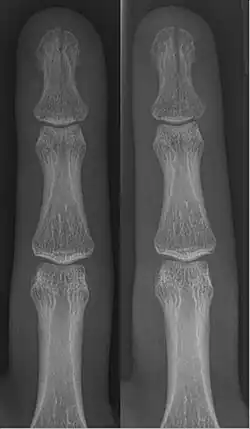

In the fingertip. More images

Linear fracture Parallel to the bone's long axis